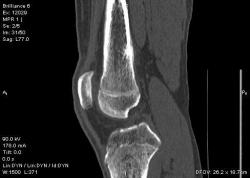

Мальчик 15 лет. Несколько месяцев назад начали беспокоить боли в коленных суставах. Травмы не было. Ребёнку был выставлен диагноз: болезнь Шлаттера, назначено лечение. На фоне лечения отмечалось значительное усиление болей, боли локализовались в левом коленном суставе. При дообследовании выявлена следующая рентгенологическая картина. Наши рентгенологи настаивают на срастающемся переломе. Но: 1) перелом без травмы? 2) бедро так не ломается

Да, на мой взгляд, состояние после обычного "травматического перелома" (трещина), не думаю, что имел место "патологический перелом", так как костная ткань "патологически изменена" минимально. "Перистальная реакция"локальная тоже есть, на КТ "локальная  зона склероза" - все это свидетельствует именно об этом. Хотя в памяти у меня хорошо отложился Ваш последний случай о локальном утолщении кортикального слоя, когда "яйца в гнезде" еще не было. То, что анамнестически "травмы не было" - ничего не значит. Вы, по всей видимости, тоже часто встречались с такими случаями, когда ребенок не акцентировал внимание на "травме", как таковой, хотя клиника есть, боль есть. Конечно, рентгенограммы - не дай бог - ни скиалогии, ни структуры.

Буквально заключение гистологов передать не могу (мой недочет, нужно было сразу выложить на сайтОй-ой-ой), но приблизительно помню - данных за специфический процесс нет, картина консолидирующегося перелома.

Так что, по всей видимости, это действительно был стресс-перелом. Который крайне редко встречается. Хоть статейку в журнал пишиУлыбаюсь.